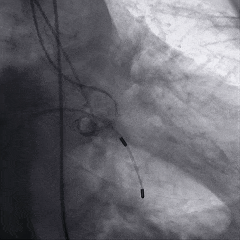

术中影像

根部造影

球囊预扩